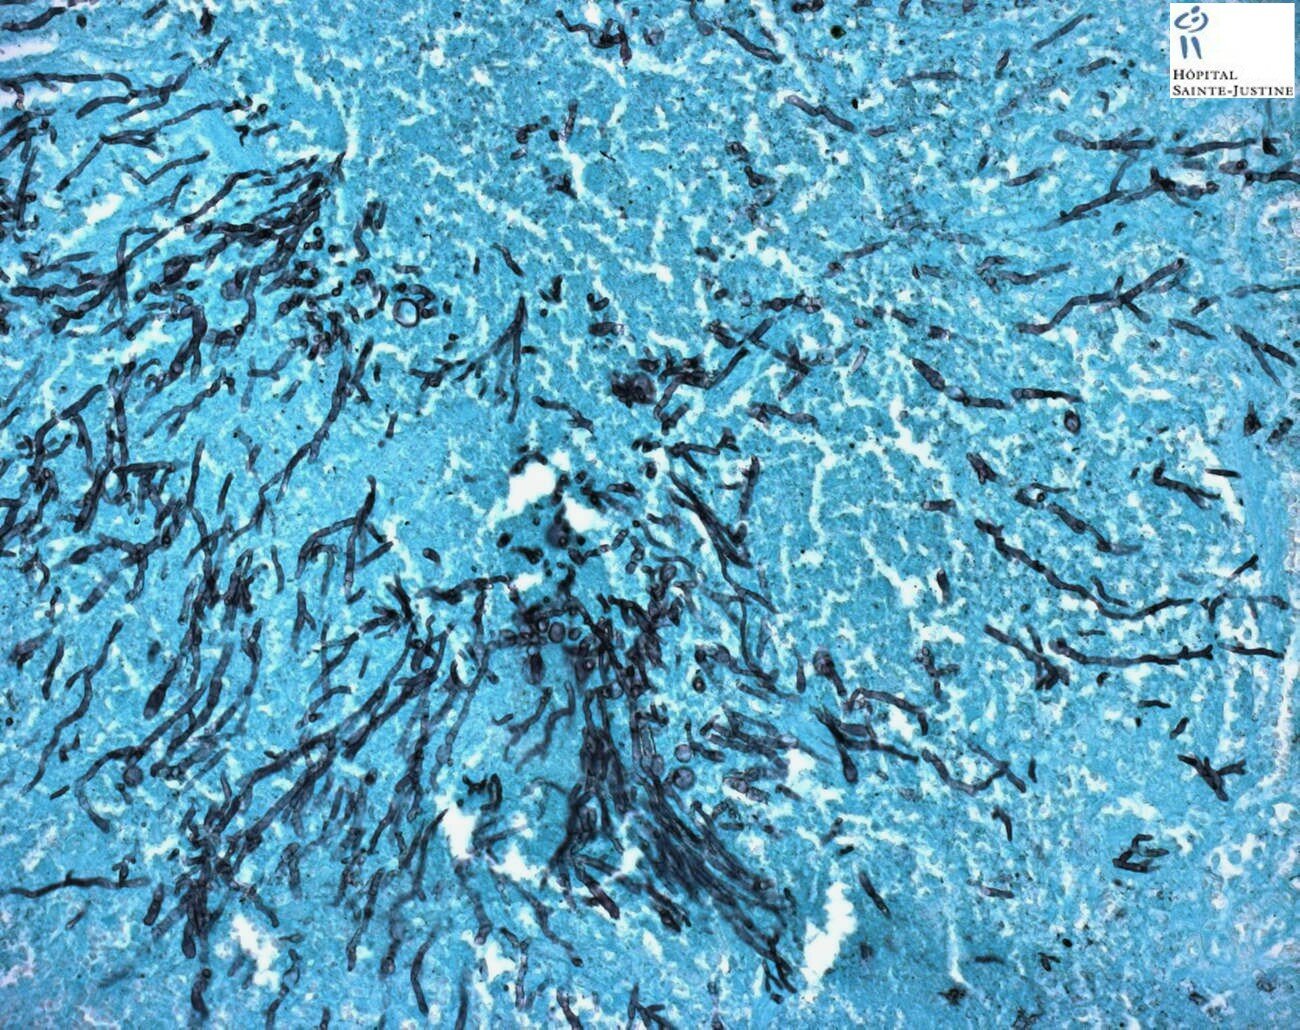

invasive pulmonary aspergillosis

Invasive pulmonary aspergillosis Invasive pulmonary aspergillosis Invasive pulmonary aspergillosis invasive pulmonary aspergillosis invasive pulmonary aspergillosis invasive pulmonary aspergillosis invasive pulmonary aspergillosis invasive pulmonary aspergillosis invasive pulmonary aspergillosis invasive pulmonary aspergillosis invasive pulmonary aspergillosis invasive pulmonary aspergillosis invasive pulmonary aspergillosis invasive pulmonary aspergillosis Invasive pulmonary aspergillosis